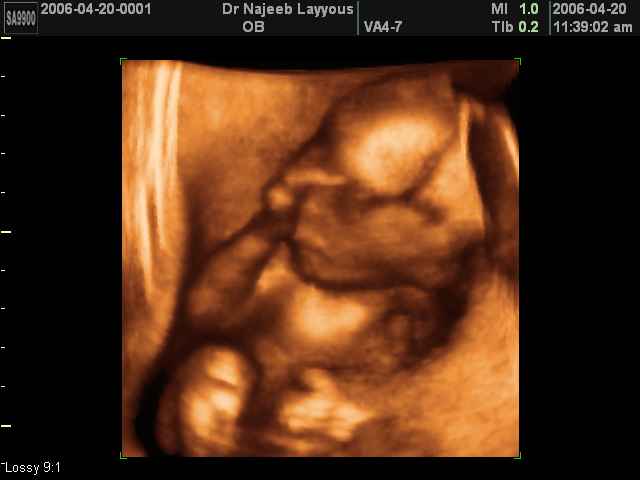

- Fetal Behavior Ultrasound Photos

Ultrasound Photos in 3D showing Fetal Behavior Inside the uterus | Dr N Layyous